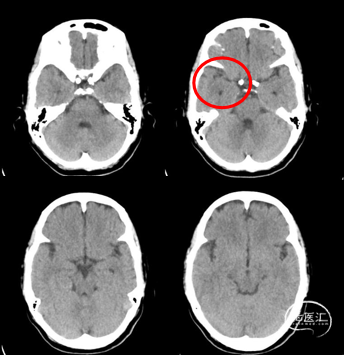

D3

2022-2-24